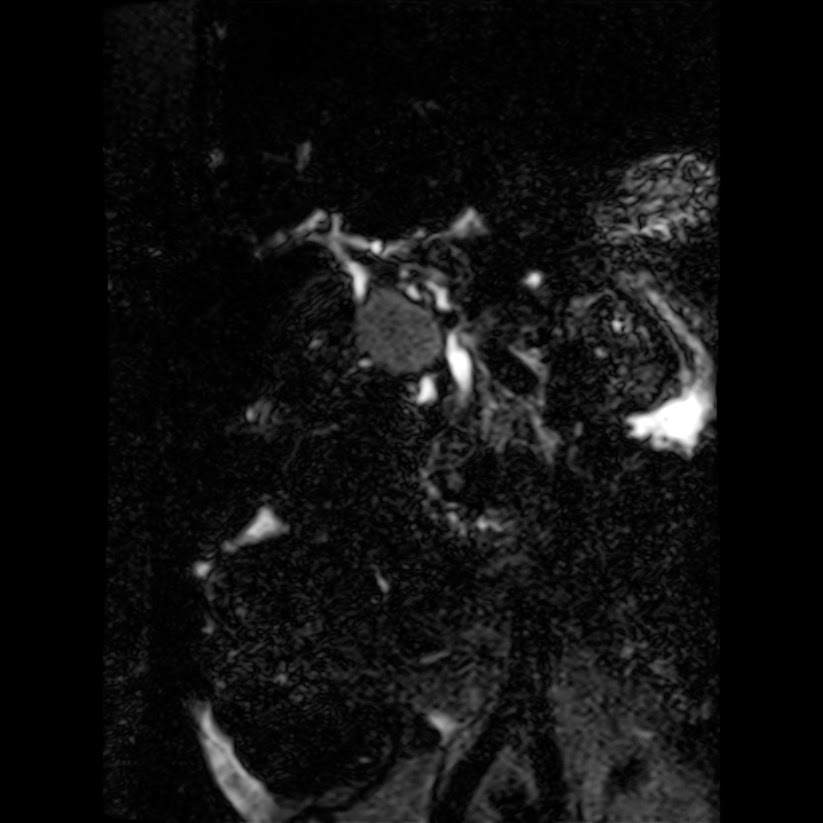

Caso interesante #5

Paciente con dolor en hipocondrio derecho.